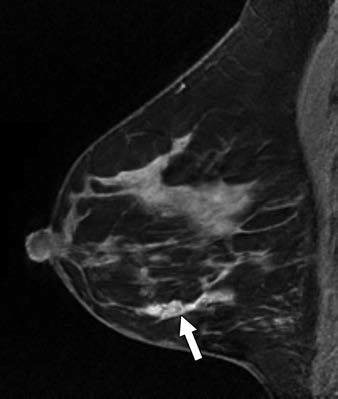

A 40-year-old woman with newly diagnosed right breast cancer presented with swelling five-months postpartum while lactating. Maximum-intensity projection MR image (above) and left breast sagittal contrast-enhanced T1-weighted MR image (below) show known multicentric inflammatory right breast cancer (arrow, above) and left breast nonmass enhancement (arrow, below) in linear distribution. MRI-guided biopsy of the left breast diagnosed ductal carcinoma in situ. Images courtesy of AJR.